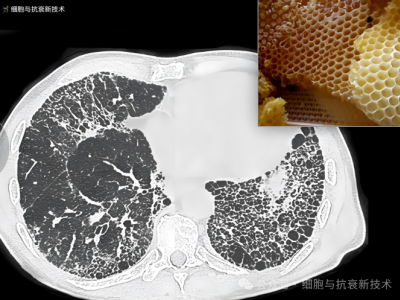

外泌體霧化可治療肺部結(jié)節(jié)及肺纖維化

2019年新冠疫情后,大家對肺部損傷比較關(guān)注,加之生活工作壓力以及檢測技術(shù)的進步,使結(jié)節(jié)成為體檢報告上出現(xiàn)的高頻詞匯,其中包括肺部結(jié)節(jié),結(jié)節(jié)的出現(xiàn)給部分人群增添了焦慮。外泌體作為先進治療藥品,是當前生